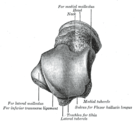

The body features several prominent articulate surfaces: On its superior side is the trochlea tali, which is semi-cylindrical,[4] and it is flanked by the articulate facets for the two malleoli.[2] The ankle mortise, the fork-like structure of the malleoli, holds these three articulate surfaces in a steady grip, which guarantees the stability of the ankle joint. However, because the trochlea is wider in front than at the back (approximately 5–6 mm) the stability in the joint vary with the position of the foot: with the foot dorsiflexed (toes pulled upward) the ligaments of the joint are kept stretched, which guarantees the stability of the joint; but with the foot plantarflexed (as when standing on the toes) the narrower width of the trochlea causes the stability to decrease.[5] Behind the trochlea is a posterior process with a medial and a lateral tubercle separated by a groove for the tendon of the flexor hallucis longus. , the lateral of these tubercles forms an independent bone called os trigonum or "accessory talus"; it may represent the tarsale proximale intermedium. On the bone's inferior side, three articular surfaces serve for the articulation with the calcaneus, and several variously developed articular surfaces exist for the articulation with ligaments.[2]

The head of talus looks forward and medialward; its anterior articular or navicular surface is large, oval, and convex. Its inferior surface has two facets, which are best seen in the fresh condition.[6]

The medial, situated in front of the middle calcaneal facet, is convex, triangular, or semi-oval in shape, and rests on the plantar calcaneonavicular ligament; the lateral, named the anterior calcaneal articular surface, is somewhat flattened, and articulates with the facet on the upper surface of the anterior part of the calcaneus.[6]

The body of the talus comprises most of the volume of the talus bone (ankle bone). It presents with five surfaces; a superior, inferior, medial, lateral and a posterior:[6]